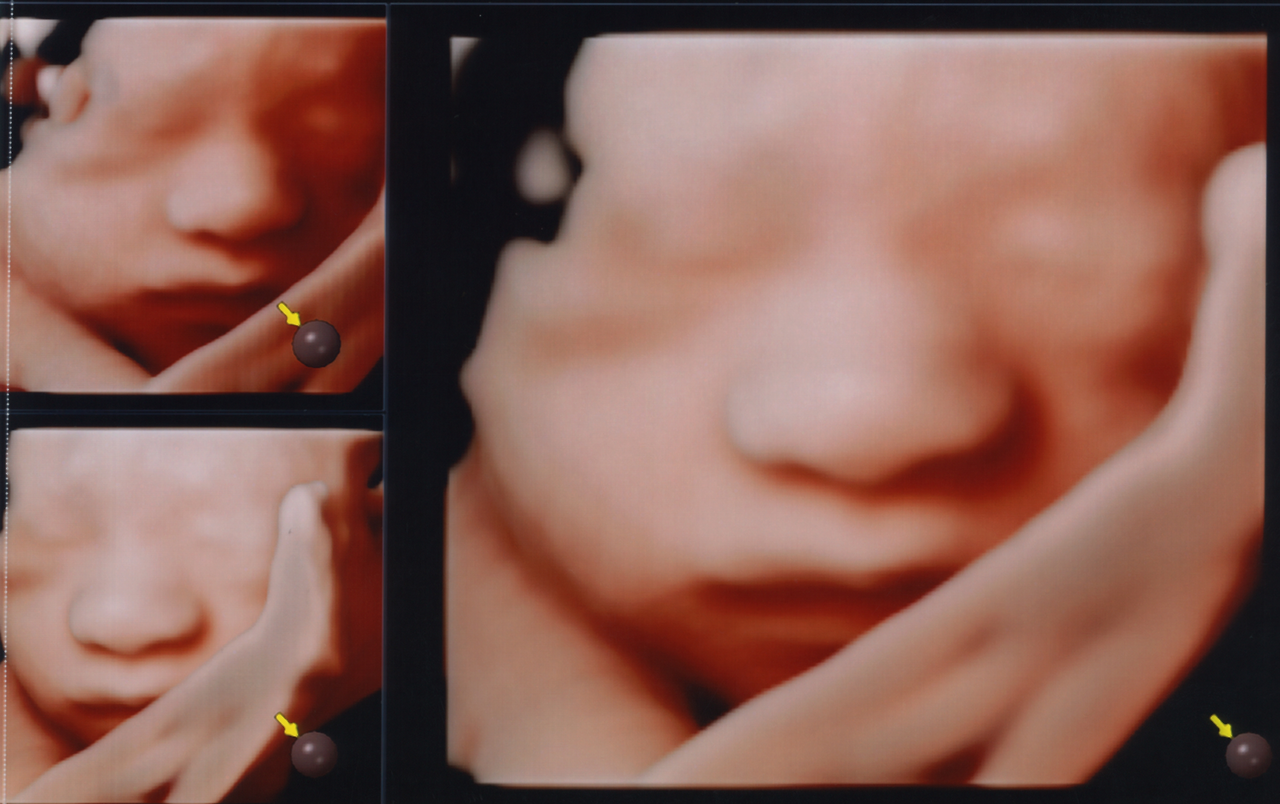

임신 초기, 중기 병원을 다닐 때만 해도 흑백 초음파에서 형체를 알 수 없는 꼬물이만을 봐서 그런지 내 아기인데도 그다지 친숙하다는 느낌을 받지 못했다. 까만 화면에서 보이는 뼈랑 장기 같은 게 가끔 해골 같기도 하고 (...) 저게 얼굴인지 엉덩이인지 어버버 하면서 찾다 보면 진료가 끝나있었다. 근데 28주 들어서 입체초음파란 걸 하고 나니 정말 내가 사람 아기를 품고 있구나가 실감 나기 시작했다.

입체초음파를 한다고 해서 아기가 바로 얼굴을 보여주진 않는다. 쉴 새 없이 팔과 다리를 움직이며 얼굴을 가리거나, 아예 등 돌려서 누워서 자고 있거나 하면 보기 힘들다. 그래서 나도 처음 한 번은 실패하고 병원 복도를 끊임없이 걸어 다니고 물도 마시며 아기의 움직임이 바뀌기를 기다렸다. 한 30분 정도 지났을까, 다시 들어간 초음파실에서 살랑이를 처음으로 마주할 수 있었다.

입체초음파.png

살랑이의 28주 입체초음파 사진.

보자마자 깜짝 놀랐던 건 제 아빠를 너무 닮았기 때문. 특히 코와 입술이 영락없이 내 남편 모습이었다. 아니 열 달 품고 있는 건 난데 왜 붕어빵 부자의 탄생이란 말인가. 첫째 아들은 엄마랑 많이 닮는다던데 그것도 아니었던 모양이다. 유전자의 신비는 둘째치고 우리 아기 피부가 정말 사람 피부색깔이라서 놀랐고, 눈 코 입 다 알맞게 붙어있는 진짜 사람 같아서 신비로웠다. 진료가 끝나고도 연신 사진을 들여다보며 우리 아기 이렇게 생겼구나, 하고 신기해했다.